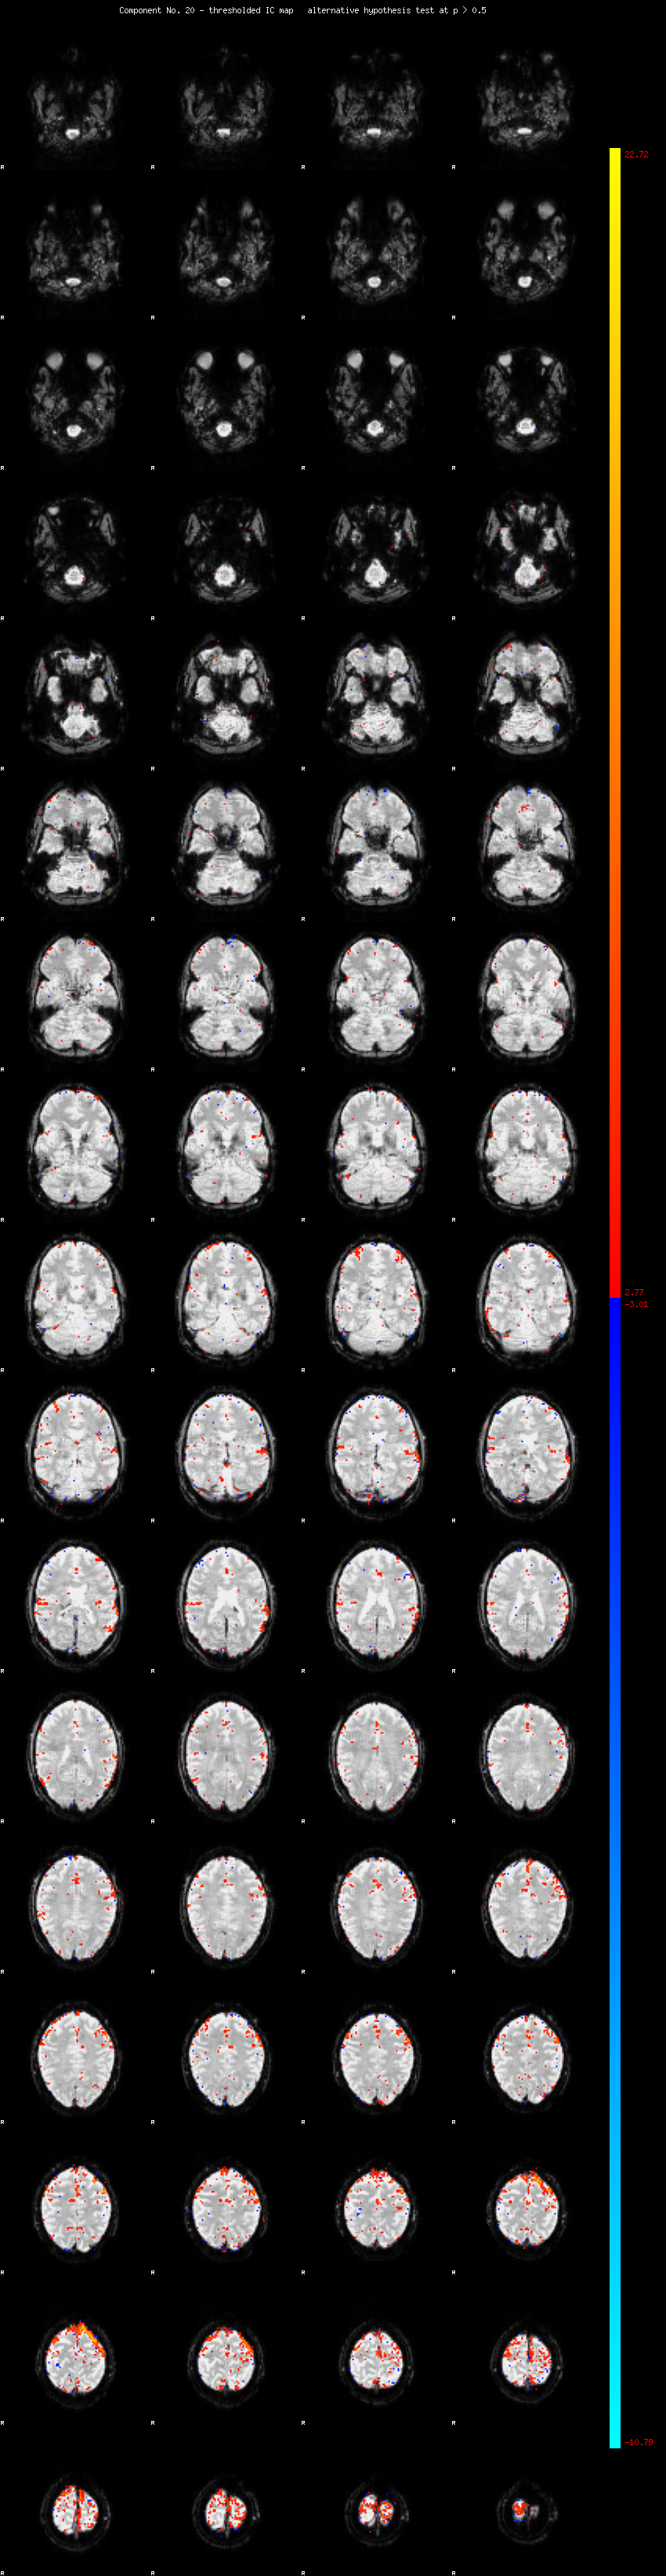

MELODIC Component 20

1.40 % of explained variance;     0.93 % of total variance